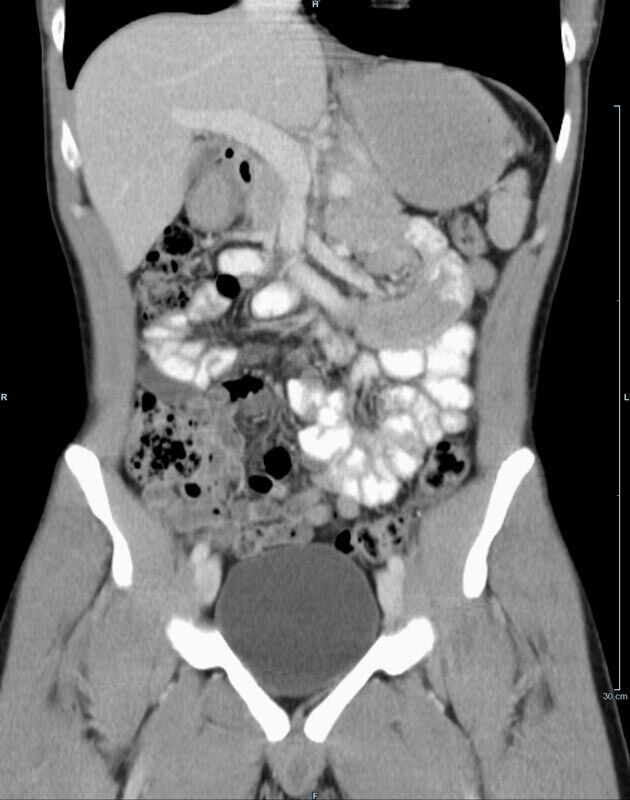

Abdomen (Bauch und Becken)

• Diagnostik von entzündlichen und tumorösen Erkrankungen der Bauchorgane

• Diagnostik von akuten Notfällen wie Darmverschluss, Hohlorganperforation oder Traumafolgen

• Darstellung der großen Gefäße zur Erkennung von Gefäßverschlüssen (z. B. Mesenterial - Arterienembolie oder Einengungen von Gefäßen (z. B. Nierenarterien)

• Darstellung und Therapieplanung von Aneurysmen (CT- Angiographie)

• Virtuelle Kolonographie zur Darstellung des Dickdarmes z. B. bei Kontraindikation zur Darm-Spiegelung oder nur unvollständig durchführbarer Koloskopie.